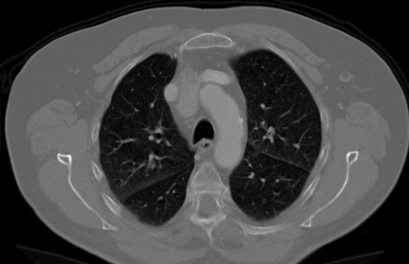

We propose a novel continual self-supervised learning (CSSL) framework for simultaneously learning diverse features from multi-window-obtained chest computed tomography (CT) images and ensuring data privacy. Achieving a robust and highly generalizable model in medical image diagnosis is challenging, mainly because of issues, such as the scarcity of large-scale, accurately annotated datasets and domain shifts inherent to dynamic healthcare environments. Specifically, in chest CT, these domain shifts often arise from differences in window settings, which are optimized for distinct clinical purposes. Previous CSSL frameworks often mitigated domain shift by reusing past data, a typically impractical approach owing to privacy constraints. Our approach addresses these challenges by effectively capturing the relationship between previously learned knowledge and new information across different training stages through continual pretraining on unlabeled images. Specifically, by incorporating a latent replay-based mechanism into CSSL, our method mitigates catastrophic forgetting due to domain shifts during continual pretraining while ensuring data privacy. Additionally, we introduce a feature distillation technique that integrates Wasserstein distance-based knowledge distillation (WKD) and batch-knowledge ensemble (BKE), enhancing the ability of the model to learn meaningful, domain-shift-robust representations. Finally, we validate our approach using chest CT images obtained across two different window settings, demonstrating superior performance compared with other approaches.